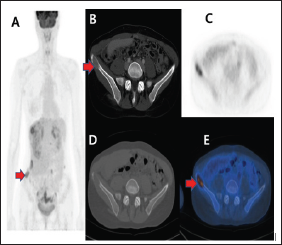

Figure 1: Abdominal pelvic CT with contrast enhancement showed osteolytic lesion in the right iliac bone (B). The maximum intensity projection PET images(A), corresponding transverse PET-CT(CD), fusion(E) showed intense FDG uptake suggesting osteolytic iliac bone metastasis.